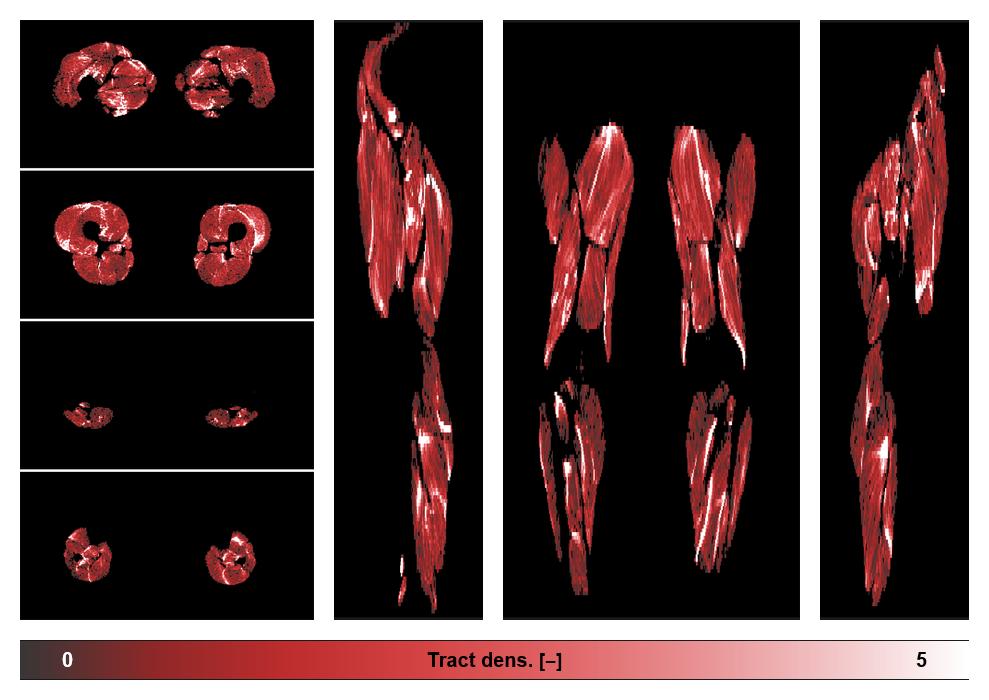

• Muscle fiber density map

Muscle fiber tract density map based on whole leg DTI based fiber tractography.